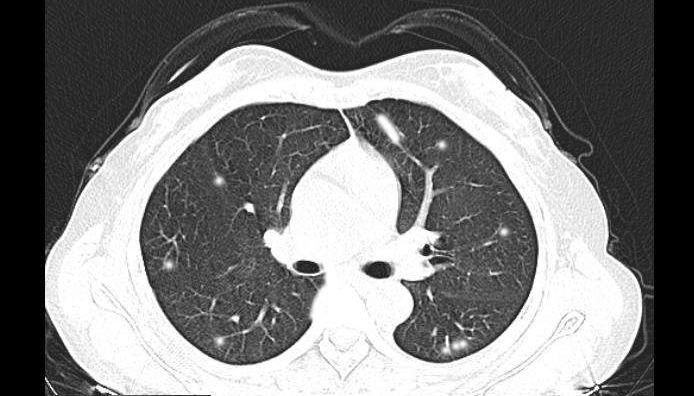

CT显示肺部呈现毛玻璃阴影,属于新冠肺炎肺部的典型特征。医院赶紧对两位患者进行了进一步排查,但是在排查的过程中让人奇怪的是,患者的血常规、病历史与新冠肺炎的症状并不相符。